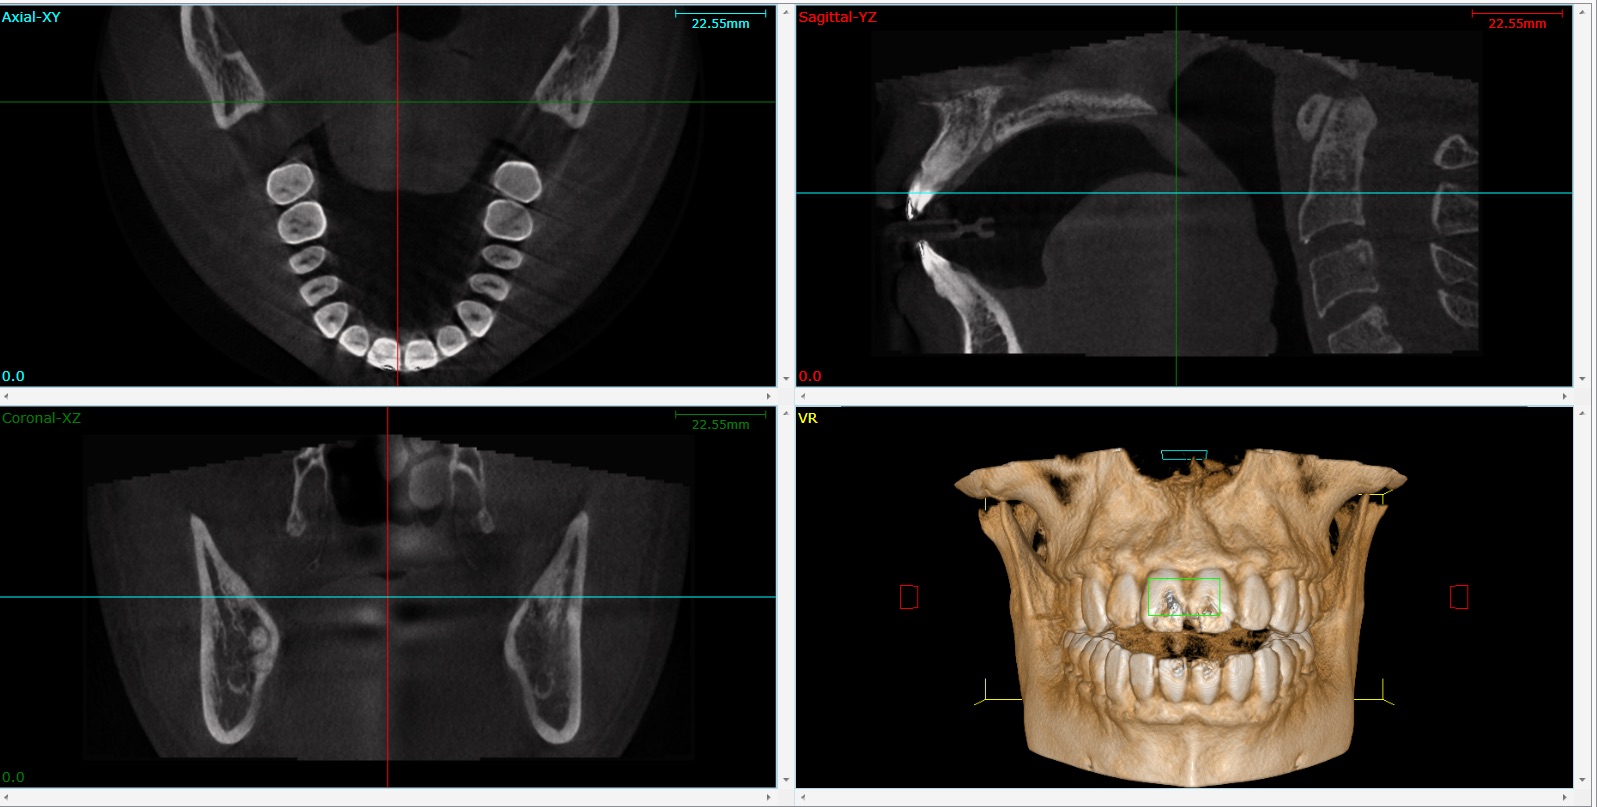

3D CT Scan Imaging for Dental Implant Surgery in Vancouver& Burnaby BC Dental Crowns And Mri Scans Web an understanding of the basic physics involved in magnetic resonance is required to appreciate the relevance of. Web you can indeed have an mri with dental crowns. Web preformed metal crowns are widely used to restore primary and permanent teeth. Web modern dental techniques use materials that do not contain magnetic material, but if the dental work is older. Dental Crowns And Mri Scans.

3D Cone Beam Computed Tomography (CBCT) · Broadway Family Dental Dental Crowns And Mri Scans Web you can indeed have an mri with dental crowns. Web modern dental techniques use materials that do not contain magnetic material, but if the dental work is older and dates back to before mris became common, patients should check with their dentists just to be sure. Web dental crowns can be made of a variety of materials, and some. Dental Crowns And Mri Scans.

Dental Cone Beam CT Scan Burbank My Dentist Burbank Dental Crowns And Mri Scans Web preformed metal crowns are widely used to restore primary and permanent teeth. Web artifacts caused by metallic objects, such as dental crowns, dental implants and metallic orthodontic appliances, are a common problem in head. Web magnetic resonance imaging (mri) has become a common and important life. Web you can indeed have an mri with dental crowns. Web modern dental. Dental Crowns And Mri Scans.